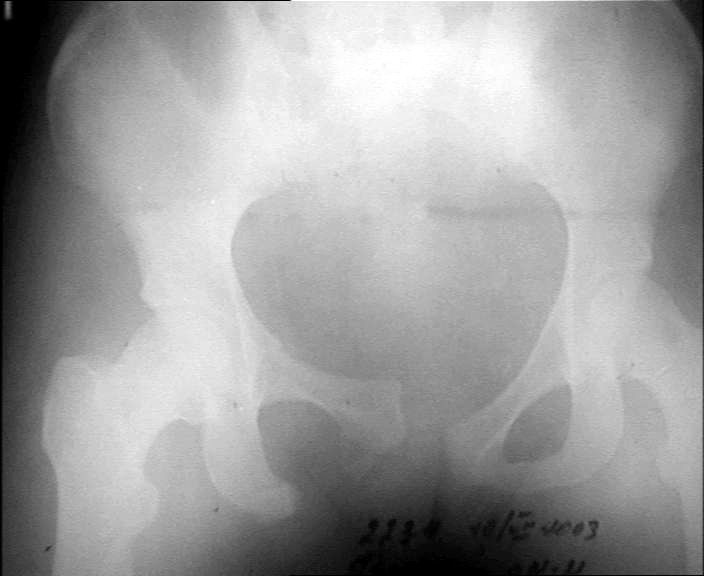

Больной 20 лет. Автодорожная авария 06.07.03.

Диагноз : оскольчатый сегментарный перелом правого бедра. Перелом лобковой кости со смещением, разрыв лобкового сращения.Планируем остеосинтез бедра пластиной. (гвоздей с блокировкой нет). Сшивание симфиза.Как поступить с переломами лобковой кости? Сергей ЗыряновНСО г. Куйбышев

Для уточнения характера повреждений задних отделов таза необходим дополнительный снимок таза в косой проекции (inlet).

Если повреждение таза ротационно нестабильное, то достаточно сдавить крылья подвздошных костей аппаратом и затем провести синтез лона пластиной

Если имеется вертикальная нестабильность, то без фиксации задних отделов не обойтись, например илиосакральный винт или кольцевой аппарат.

Такое смещение в переднем отделе невозможно без повреждения задних отделов, а стабильность таза в основном они и обеспечивают. Что-то там неладно в области правого крестцово-подвздошного, и смещение по вертикали есть. Снимки плохого качества, трудно разглядеть, на перелом крестца похоже. Сдлать бы еще и inlet, то есть фас с направлением луча с краниальной стороны градусов 30-40 от вертикали.